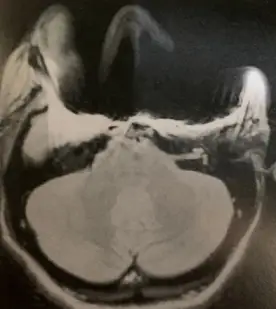

有一位女性病患作腦部磁振造影檢查如下圖,掃描後在影像的下顎整個範圍出現大片全黑的訊號,此時應為:

觀察題目提供的腦部 MRI 橫斷面(Axial)影像,切面位置大約在小腦與下顎/口腔的高度。在影像的下顎及口腔前方區域,出現了一大片完全無訊號的「全黑區域(Signal void)」,並且在黑影的邊緣伴隨著極度明亮的高訊號堆積(Signal pile-up)與嚴重的幾何扭曲(Geometric distortion)。 這類「大面積黑洞合併周邊扭曲亮邊」是極度典型的**金屬磁化率假影(金屬假影)**特徵。在下顎與口腔周圍出現此類假影,臨床上最常見的原因就是病患口內有金屬植牙、金屬牙套、矯正器或活動式金屬假牙。